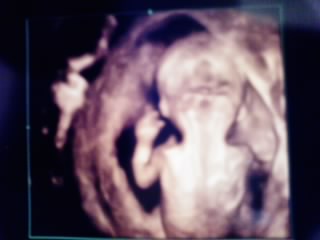

昨日は旦那ちんと一緒に「胎児ドック」を受けに行ってきました。2人で話し合って羊水検査を勧められたケドも、ワンクッション置いて…の予定だった採血。トリプルマーカーやクアトロテストが私の周りでは受けられないので検索魔になって調べてると、「胎児ドック」を発見前日からドキドキだったんだけど、行って見るとクリニックって感じのしない静かな環境と、スタッフの気さくさにリラックス♪でき…実際のエコーは旦那ちんも立会い、食い入るように見てました(笑)うちのチビちゃん、とっても元気でピョコピョコ動き回ってなかなか、先生の見たい場所を見せてくれなかったり、映すたんびに変な格好するから、みんなに笑われたり…ひょうきんモノ…???「お父さん似かもよ~笑」とか「この子テレビに映る素質もってるんちゃう?」まで言われる始末…☆頭の先から、足の先までじっくり見てもらったけど、今のところ特に異常はないとのこと。1つ、羊膜がはっきり分からないって言われたけど今ひとつ私には何のことやら…てか、元気なのが嬉しくて先生の話が筒抜けてたのかも…スミマセン少し、心配ですがチビちゃんの体には問題がなくて、ホントにホントに……一安心です~~~~~~~そして、まだ早すぎるんやけどエコーでのはじけっぷりからチビちゃん…男の子疑惑…笑でも、先生もはっきり言ってくれないけど男の子を臭わすようなコト言ってたんだよね~。ついてたのかな!?笑でも、あれだけエコーで詳しく詳しく見れるんだからすでに生殖器がどうってのも、十分分かりそう!!何たって、心臓の血流だとか・臍の緒の血流まで分かるんだもん。現代の医学はすごい…。てか、先生すご~って感じ。私が不安いっぱいだったのを察してかすっごく分かりやすく丁寧に教えてくれたしアットホームな雰囲気もいいし、思い切って受けに行って本当に良かったと思います旦那ちんも、初めて我が子との対面に感動したらしい。看護婦さんに「パパ」って呼ばれて照れくさかったんだと☆エコー写真見てニヤニヤしてる旦那ちん見たら私もニンマリコレ↑↑↑後姿ですが左手挙げて「やぁ」って感じ!??さて…羊水検査はどうしよう。。。私的には、ここまで見てもらったからいいかなぁと思うんだけど旦那ちんは、考え込んでる様子…。難しいなぁ☆

早いもので11週に突入しました。来週には4ヶ月ってコトですよね!!??何か響きがいいゎ~ よくココまでこれたものだと自分でも驚きです先週の木曜に診察を受けたけど、やっぱし待ち遠しいと言うか早くチビたんに会って安心したいというか…。 健診の時は朝から落ち着かないモンです…。 今日のエコーは前よりじっくり見て下さいました♪チビは4cm!!拡大されてかなり大きく見える(笑) もぅ、お腹の中で自分で手足をバタバタさせてるんだぁ~と感動 頭から足までよ~く見てもらって、心配だったNTも今のところ問題なさそうです^^ しかし…。 問題もまだまだあって、 1.風疹抗体がえらく高値…精査になってしまった。万が一感染なんてしてたらどぅしよぅ… 2.出血は前よりは落ち着いているけど、まだ残ってる。1ヶ月は安静!!??(長すぎ…) 20週前後までこの血腫が残るようなら、大きい病院での出産の方が安全とまで言われる始 末…涙 3.初期の成長の遅れで前医に勧められた染色体検査。。。中でも負担の少ないクアトロテス トを先生からは勧められたんだけど、今の病院ではしてないので、自力で探して受けろと のこと。 やっぱし、羊水検査が確実みたい…。 なんか、心配事の方が多い!???? どれもこれも考え出すと頭が痛い…。1つずつ良い方向へ進むといいなぁ~。 祈るしかないよね!!ナムナムとにかく、我が子が元気で何よりです♪

昨日、エコーを見てもらいました。数日前からお腹の張りと、生理痛みたいな痛みがあったもんで…。10w4dでおチビは3.4センチになってました心臓の音も初めて聞かせてもらって感動力強い鼓動が聞こえてきて、泣きそうになりましたそこまでは良かったのですが…気になってた出血…。やっぱしまだお腹の中に残っててそれも、結構な量ですと。。。来週からの仕事復帰に向けて動いてると伝えたんですがもぅ少し安静にしてるようにと言われてしまいました…まさか、新たに出血するなんで思ってなくて徐々に消えていくものだとばかり思ってたんで再び先生から安静を言い渡され…ベビちゃんに申し訳なくて凹みました ゴメンネ☆ゴメンネりりちゃんから、起きてるだけでも負担が…と前に聞いたのでできるだけ、横になって少しでも早く居心地のいい子宮にしてあげたいです。。。

まさか、こんな日が来るとは…。ずっと、婦人科でかかってた近所の産婦人科。「ここでお産できたらいいなぁ」って思ってたのが1年半前くらいかなぁ~。「妊婦検診初めてですよね?」ってコトバにドキドキしました。そして、まだやっぱしエコー見るまで我が子が無事かそれが心配で心配で…。ちゃんと元気に生きてました今日は頭と胴体が結構ハッキリわかって2頭身…かゎいい…ここまで成長してくれてエコー見ながら泣きそうでした。ってか、入院先の病院のエコーはなんか映りが悪かったんじゃあ!??って思うくらい、帰ってから見比べても分かりニク…。まだ赤ちゃんの周りに血腫がいくつかあるみたいで出血してくる可能性はあると言われましたが…気をつけよう…。無理はしないでおこう…。大丈夫だろうって思って行動するのに自制をかけよう…。色々頭の中を過ぎりました。次回は5月12日。11w1dの日になります!!結構長いよね…